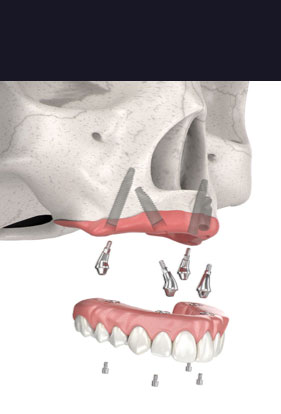

For patients who have experienced jawbone deterioration but still have strength in their upper-jaw, Pterygoid dental implants could be an effective option for a teeth-in-a-day procedure.

Through Pterygoid dental implants, our dental implant specialists will place 15 to 20 mm implants in the dense part of the Pterygoid bone. This eliminates the need for bone augmentation and helps patients with severe bone loss avoid Zygomatic implants if possible.